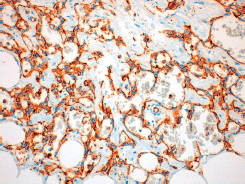

The histological diagnosis of moderately or poorly differentiated radiation-induced angiosarcomas is relatively straightforward. It shows factor VIII and PECAM-1 (CD31) immunostaining positive malignant endothelial cells (Figure 3) which form vascular channels and extend into the surrounding stroma [15]. Well-differentiated angiosarcomas can be difficult to diagnose and have to be differentiated from hemangiomas and from atypical vascular lesions that appear after radiotherapy [16]. These latter lesions do not usually exhibit elevated mitosis or cellular atypia, although the cells may be hyperchromatic and form anastomotic vascular clusters with varying degrees of inflammation [15]. It is worth noting that in radiation-induced angiosarcomas, there is an increased v-myc myelocytomatosis viral oncogene homolog that does not exist in the atypical vascular lesions. This could be used to reach the diagnosis in complex cases or before limitation of available tissue [4].

Figure 3. 20x amplification of the definitive anatomopathological study of our case where the positivity of CD31 is observed.